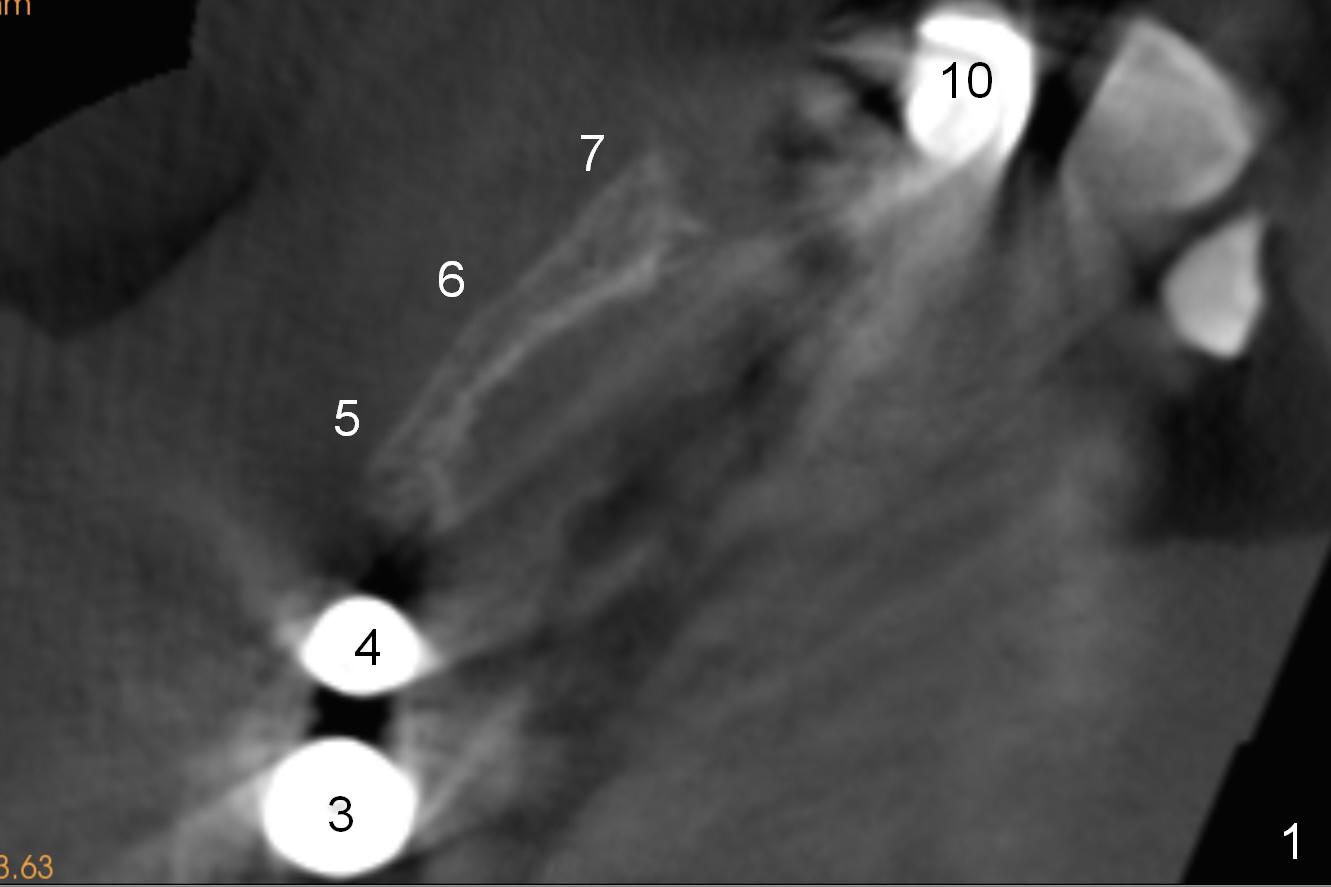

CT scan taken 10 days post immediate implant placement at #3, 4, and 10 shows that the edentulous area is narrow (Fig.1 (axial section), 2-6 (coronal sections; B: buccal)). In addition, the bone density is 100-200 Hounsfield units (Fig.2). Osteotomy should be underprep: 1.2 mm to the depth; 1.5 mm haft the depth. It appears that 2.5 or 3.0 mm 1-piece implants can be placed at #5,7 and 8 (Fig.3,5,6). Check buccopalatal trajectory after each step of osteotomy using surgical stent. Insert a 3 mm dummy implant tentatively. If it looks too wide for the ridge, use a 2.5 mm implant. If trajectory is off, use an angled one, especially at #7 (Fig.5).